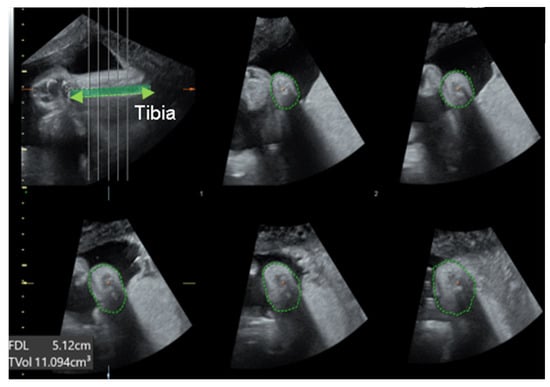

2.3. Sonographic Measurements

| Volume of calf (cm3) a | 5.16 (3.57–8.68) | 6.59 (5.7–8.18) | 0.257 |

| Circumference of calf (cm) a | 6.5 (5.79–8.03) | 7.68 (7–8.8) | 0.073 |